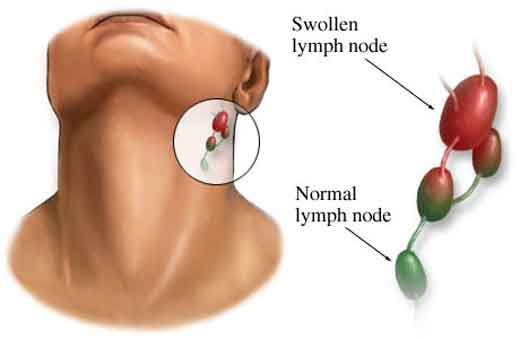

Cosa sono le sindromi linfoproliferative Le patologie linfoproliferative sono un gruppo secondario di patologie che interessano gli organi linfoidi secondari; il primo gruppo sono i linfomi Hodgkin e Non-Hodgkin. Principali sindromi linfoproliferative Le principali...